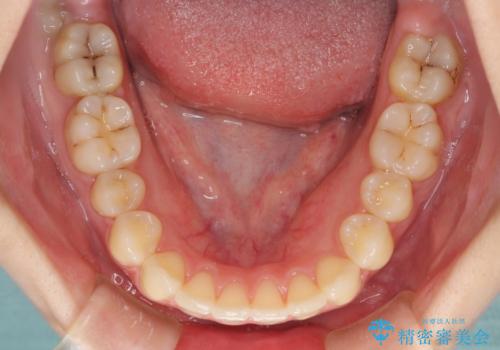

- 上下前歯のデコボコを気にして来院された患者様です。

以前矯正をした後戻りということで、歯列不正はそれほど大きくなかったため、インビザライン・ライトを用いて矯正治療を行うこととしました。

前歯のデコボコが残っており、シミュレーション通りに動いていない部分がありましたが、再矯正であることやご本人の満足いくところまでデコボコが改善されたとのことで、治療を終了することとしました。